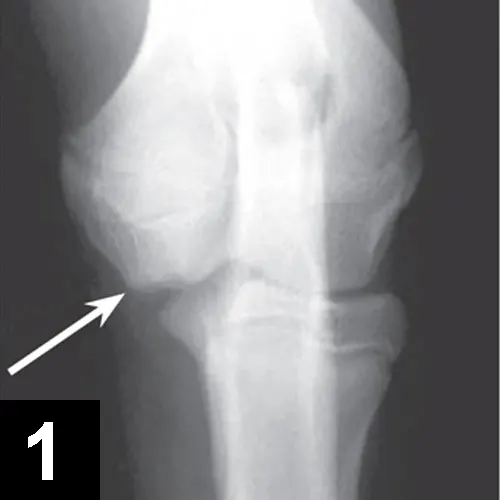

• Orthogonal radiographs may confirm diagnosis, especially with OCD lesions (Figures 1 and 2).

X-ray of a dog’s elbow with arrows pointing to lesions.

FIGURE 1

Craniocaudal view of an elbow with OCD lesion (arrow).